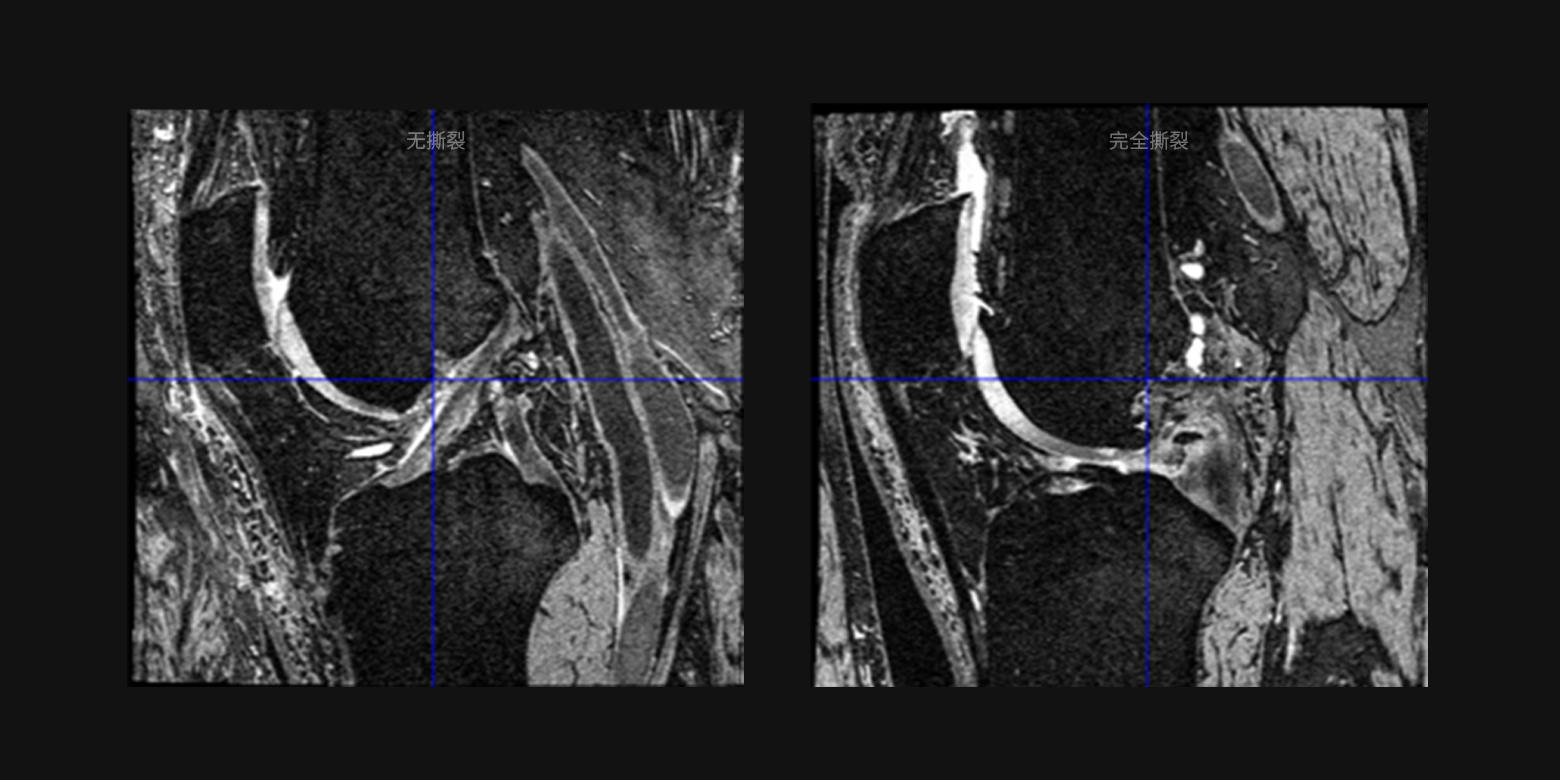

病灶良恶性鉴别与疾病分级

基于对复杂医学诊断要素的学习,支持多种病灶的良恶性鉴别或病情分级,例如十字韧带撕裂分级、肺结节良恶性鉴别等,满足疾病大范围筛查、分级诊疗等多种场景需求。